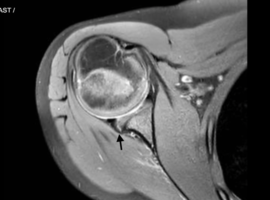

Citation: Anderson K. Percutaneous Labral Repair Using Nanoneedle in a Pediatric Baseball Player. Case Rep Orthop Surg J. 2026; 5(1): 156.